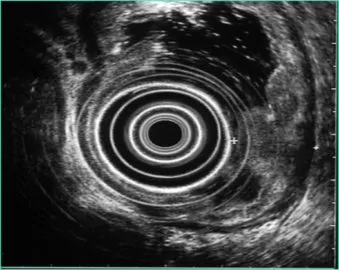

Второй выступающий – заведующий эндоскопическим отделением, к.м.н. Станислав Юрьевич Орлов поделился с собравшимися подробностями применения такого сравнительно нового метода эндоскопических исследований, как ультрасонография пищеварительного тракта, с помощью которой нашим врачам удается диагностировать

десятки различных заболеваний, включая язвенные кровотечения, кистозные образования поджелудочной железы, острый и хронический панкреатит и даже

карциноиды. С апреля 2017 г. в больнице было проведено более 80 ультрасонографических исследований.